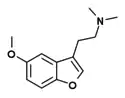

Dimemebfe | 2-(5-Methoxy-1-benzofuran-3-yl)-N,N-dimethylethanamine | 140853-58-3 |